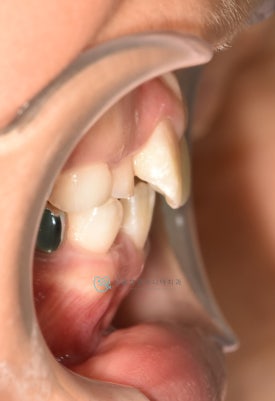

치료 전 - 위아래 심한 공간 부족이 관찰됩니다.

아이는 위 아래 심한 공간부족으로 인한 어린이덧니가 관찰됩니다. 공간부족으로 인해 앞니가 삐뚤빼뚤하게 나왔으며 곧 나올 위 두번째 앞니도 회전되어 맹출이 예상됩니다.

치료 전 - 위아래 심한 공간 부족이 관찰됩니다.아이는 위 아래 심한 공간부족으로 인한 어린이덧니가 관찰됩니다. 공간부족으로 인해 앞니가 삐뚤빼뚤하게 나왔으며 곧 나올 위 두번째 앞니도 회전되어 맹출이 예상됩니다.